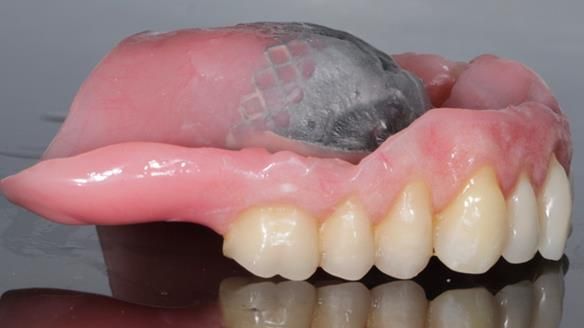

The detailed clinical situation and treatment process are outlined below, with clinical work provided by me and technical work by Rowan Garstang. The treatment spanned 12 months, involving removing 5 upper anterior teeth, adding to an existing upper RPD, followed by creating and fitting metal based complete dentures.